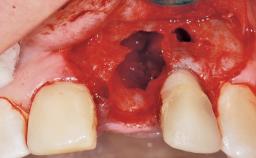

A 39-year-old male patient presented with a chief complaint of discomfort and gingival discoloration around his maxillary left central incisor. He was in good general health and was a non-smoker. His past dental history was significant because of the traumatic fracture of tooth 21 in a sporting accident at age 13. Initial dental treatment included endodontic therapy and a full-coverage restoration. The patient became symptomatic 5 years later, when structural failure of the tooth resulted in the dislodgment of the crown. Endodontic retreatment, apical surgery, and post-and-core restoration were performed.

Bone Augmentation Horizontal|Staged

Augmentation Materials Xenogenous|Membrane

Soft Tissue Anatomy Intact Defective

Bone Volume Horizontally and vertically sufficient Horizontally deficient Deficient vertically or deficient vertically AND horizontally

Bone Volume Deficient horizontally, requiring prior grafting